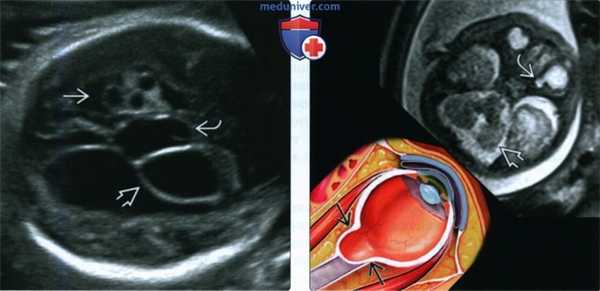

(Слева) УЗИ плода женского пола в III триместре, поперечная плоскость. Визуализируются несколько пороков развития головного мозга: кисты сосудистого сплетения, внутрижелудочковая и межполушарная кисты, АМТ и аномалия развития мозжечка.

(Справа) МРТ того же плода, Т2-ВИ. Левое полушарие мозжечка уменьшено, определяется колобома диска зрительного нерва. На рисунке изображен классический вариант колобомы диска зрительного нерва - дефект в задней части глазного яблока в месте выхода зрительного нерва. У новорожденного диагностирован синдром Экарди.

(Слева) При МРТ Т2 FS в аксиальной проекции визуализируется уменьшенное левое глазное яблоко с обширной задней колобомой. Непосредственно позади глазного яблока в жировой клетчатке глазницы определяются две отдельные сопутствующие колобоматозные кисты.

(Справа) У младенца с множественными врожденными аномалиями при MPT Т2 FS в аксиальной проекции в заднем полюсе деформированного глазного яблока малых размеров определяется мелкий колобоматозный дефект. Видна крупная сопутствующая ретробульбарная киста.